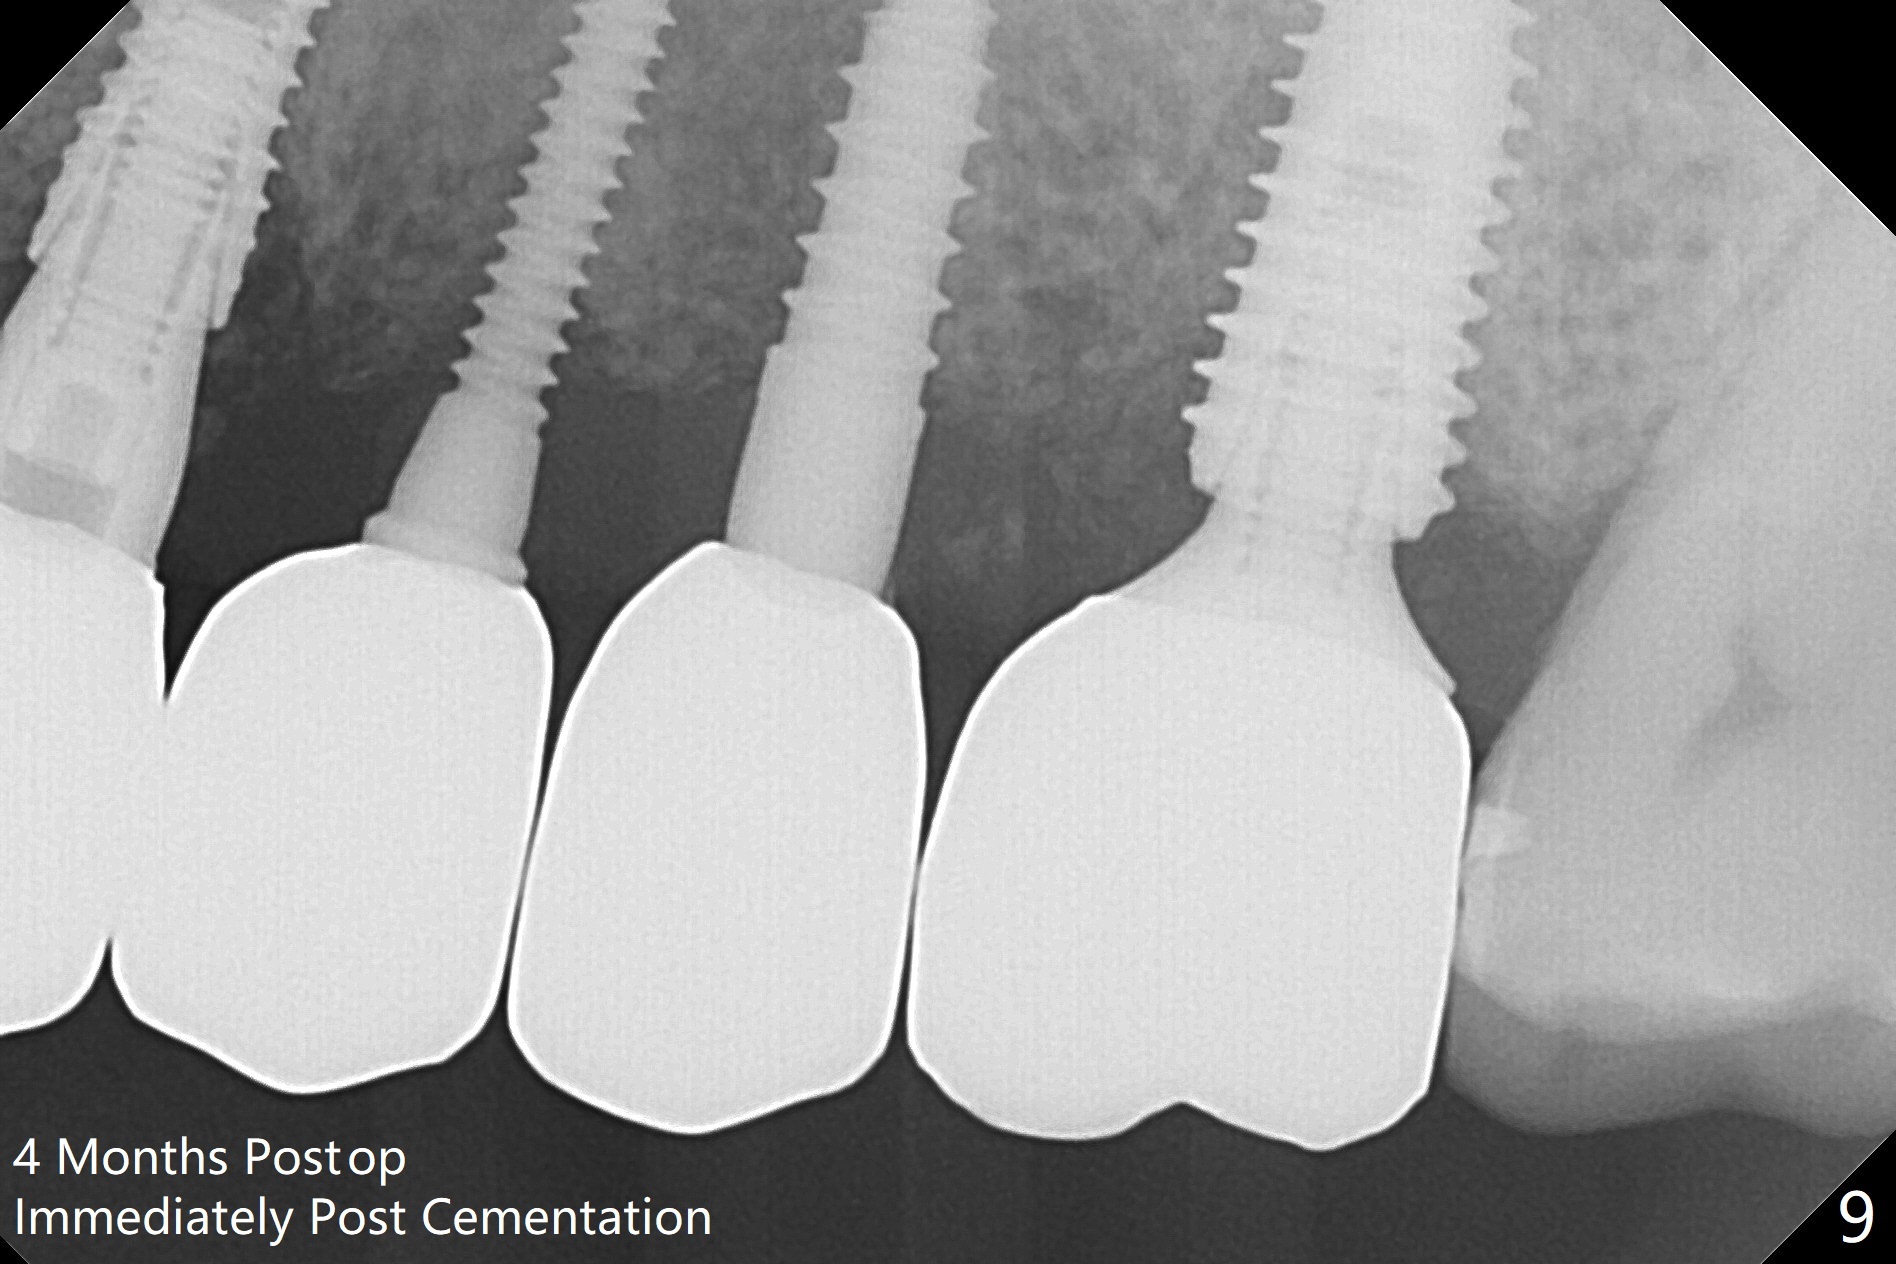

The edentulous ridge is narrow between the residual roots of #11 and 14 (Fig.1). Since the bone density is low in the edentulous area, DIO bone expanders are used (e.g., #1 (1/1.6 mm) Fig.2) after 1.2 mm initial drill. A 2x14(2) mm 1-piece implant is placed at #12 with 4 mm ridge width, while a 3x10 (2) mm dummy implant is partially placed after use of Bone Expander #2 (1.3/2.3 mm). The latter is replaced by a definitive one (3x12(2) mm), while the one at #12 is placed deeper (Fig.4). After extraction and placement of PRF and Vanilla Graft for sinus lift (Fig.4 black *), a 5x10 mm 2-piece implant is placed at #14, while a dummy implant is placed at #11 (Fig.4,5). As the osteotomy at #11 is 4.9 mm longer than the dummy (Fig.5), a definitive one is 3 mm longer (Fig.6). Osteogen plug is placed in the apical portion of each socket at #11 and 14, while Vanilla and Osteogen are packed in the coronal portion of the socket (Fig.4,6 *). Although primary stability of each implant is not high (30/40 Ncm), splinted provisional with occlusal clearance seems to be sufficient for implant osteointegration. There is no discomfort 9 days postop (Fig.7). Impression is taken 3 months postop, since he plans to return to home country for business (Fig.8). Single unit crowns are cemented 4 months postop (Fig.9,10). The abutment screw at #14 needs retightening 6 months post cementation. The access hole slightly buccal. Chewing pain at #12 is reduced after occlusal adjustment 6.5 months post cementation (Fig.11).